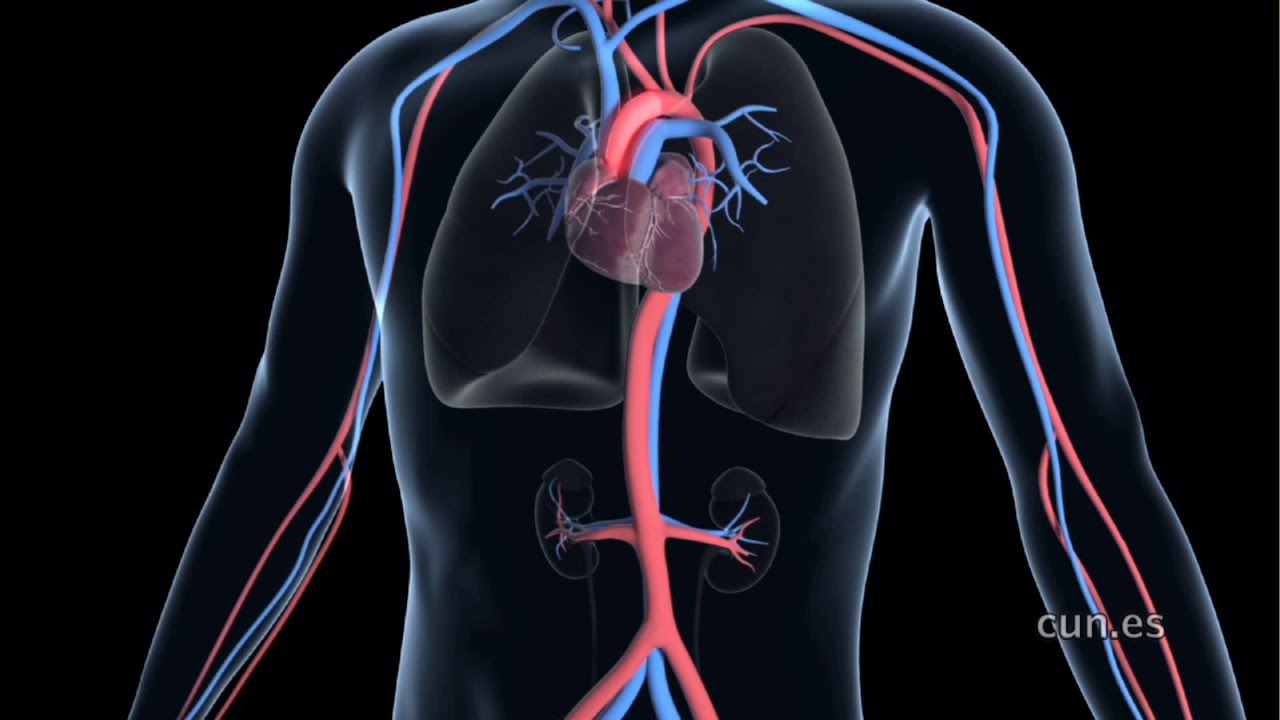

Riesgos infecciosos asociados a los fármacos biológicos utilizados en enfermedades inflamatorias de origen inmune.

El riesgo asociado a las terapias inmunosupresoras se deduce en muchas ocasiones de su mecanismo de acción y establecer una relación causal a veces es complicado. el  objetivo de este boletín fue revisar la evidencia disponible acerca de los riesgos infecciosos relacionados con los fármacos biológicos utilizados en las enfermedades inflamatorias de origen inmune.BIT Navarra, 31 de agosto de 2020